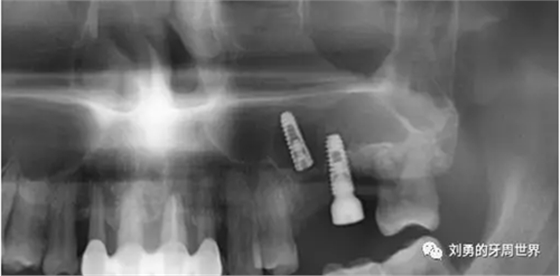

內(nèi)提升植骨后4個(gè)月,在外院行種植體植入,B5植入種植體3.5X10mm,B6植入種植體4.0X10mm,術(shù)后4個(gè)月后行二期手術(shù),術(shù)中B5種植體松動(dòng),未敢處理,B6放置愈合基臺(tái)。二期手術(shù)前復(fù)查ct如下圖(可見(jiàn)B56種植體竇內(nèi)成骨很少,種植體距離過(guò)近):

由于患者已經(jīng)接受兩次手術(shù),原種植醫(yī)生喪失信心,因此轉(zhuǎn)診給筆者,在二期手術(shù)后4天決定取出失敗種植體。并試圖重新種植??梢钥吹街暗膬蓚€(gè)種植體位置過(guò)近,位置不理想。